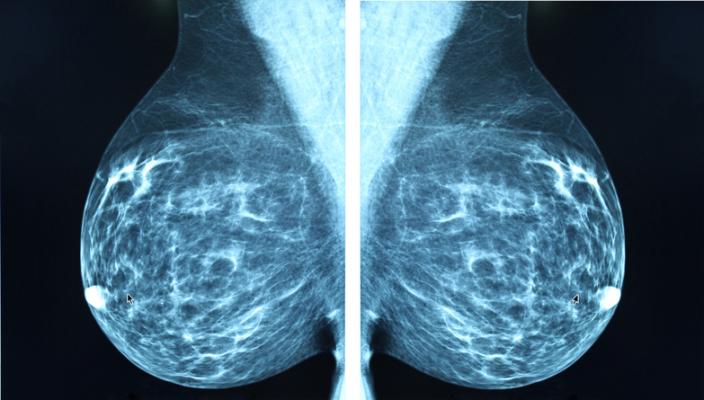

Getty Images

March 3, 2021 — Attendance at regular mammography screening substantially reduces the risk of dying from breast cancer, according to a large study of over half a million women, published in the journal Radiology. Researchers said women who skip even one scheduled mammography screening before a breast cancer diagnosis face a significantly higher risk of dying from the cancer.

Breast cancer screening with mammography has helped reduce disease-related deaths by enabling detection of cancer at earlier, more treatable stages. Despite mammography's well-established effectiveness, many women don't participate in recommended screening examinations.